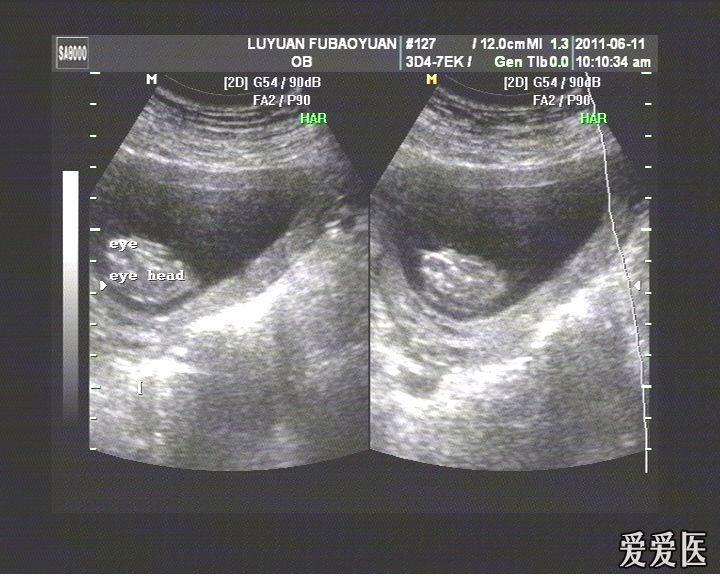

胎儿无脑畸形2d4d图

图片尺寸720x576

胎儿无脑畸形

图片尺寸407x303